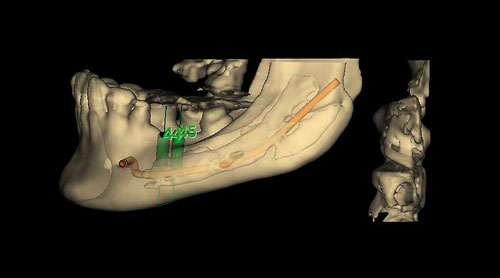

Mientras dichos movimientos ortopédicos se producen (período que supondrá otros seis meses), estudiamos los actos quirúrgicos a realizar en los cuatro implantes que pondremos. De acuerdo al estudio Desatascan realizado observamos tres situaciones diferentes: 1º-El Primer Molar Inferior Izquierdo, lo instalamos mediante Cirugía Minimamente Invasiva , con la aplicación de una Férula Quirúrgica Obtenida de los datos del scanner tratados con un programa de CMI (Cirugía Minimamente Invasiva), previa prueba en un modelo estereolitográfico, ya que la altura ósea era apenas de 9 mm. 2º- El Primer Molar Superior Derecho, se implantará mediante una ligera Elevación Atraumática (Trans alveolar) de Seno una vez logrado el espacio mesio distal necesario. 3º- El Incisivo Central Superior Derecho ausente, cuenta con un sustrato óseo prácticamente inexistente. El espesor de la tabla era de menos de 2 mm. Los caminos posibles a seguir para contar con una Rehabilitación de piezas independientes son dos: Optamos por esta segunda opción por ser menos cruenta y no necesitar de una zona dadora. Técnica esta que pondremos en práctica en dos etapas diferidas: 1º-Incisión horizontal palatinizada, incisiones peri rodetes gingivales e incisiones de descarga. Dilatación que comenzamos con dos incisiones de descarga sobre la cortical vestibular realizadas con disco. y el comienzo de la dilatación propiamente dicha mediante una hoja de bisturí, para luego seguir con un periostótomo . Recién después de alcanzada una cierta separación de la cortical vestibular de la palatina, empezamos con los dilatadores roscados. En este punto podríamos haber utilizado sin riesgos un Implante de 3,8 mm de diámetro, pero a fin de mejorar la estética del pilar emergente decidimos rellenar con material osteoconductor y osteoinductor (BiOss) y cubrir mediante membrana reabsorvible ( Bio Guide). 2º-Implantación seis meses después. Mientras se van cumpliendo los tiempos antes mencionados, y comprobamos reiteradamente la funcionalidad de la oclusión con los provisorios, tomamos impresiones definitivas y construimos primero el maxilar inferior, para definir en primer término la porción inferior de la Guía Anterior., y a nivel posterior Curvas y Microplanos. Para luego realizar los cuadrantes premolar- molar del superior: La espera de la regeneración ósea y sus tiempos pertinentes, más la espera de los tiempos de la implantación, nos obligaron a modificar las etapas del protocolo D.AT.O de manera de mantener la –D- mediante el sector superior de la GA. en provisorios, mientras fuimos resolviendo en forma definitiva los demás sectores. Ya pasados los meses necesarios para recrear un hueso adecuado en el área del Incisivo Superior Derecho, procedemos a resolver la implantación de dicha zona, observando que todo el esfuerzo dedicado al mismo había sido inútil, ya que la formación de hueso se produjo minimamente. Cuatro meses después tomamos impresiones del sector Antero Superior de la Guía Anterior, incluyendo el arrastre de un transfer . Seguimos modelando la encía con un nuevo juego de provisorios. Y se construye entonces el sector superior de la Guía Anterior. Se efectúa un control radiográfico a los 6 meses. Se ha intentado mostrar en esta Rehabilitación, que a pesar de las distintas circunstancias de cada paciente, siempre debemos tener en cuenta la necesidad de ejercer la DESOCLUSIÓN del caso como prioridad número uno, para luego perseguir la ALINEACIÓN TRIDIMENSIONAL de las arcadas y obtener así una OCLUSIÓN equilibrada. D.AT.O. ES EL PROTOCOLO QUE DEBEMOS SEGUIR EN TODA REHABILITACIÓN. BIBLIOGRAFÍA 1)William Mc Horris,B.S.,D.D.S. Oclusión. Con especial énfasis sobre :El rol funcional y parafuncional de los dientes anteriores. 2)Von Spee , Craff(Anatomista alemán, describió la curva de compensación de la articulación de molares y premolares).CURVA DE SPEE 1.89 3)Stuart,D.”Some aspects of the inervation teeth.”Procedings of Royal Society of Medicine.20:1675,19274)Muhleman,H. y Savdir,S”Tooth movility-its causes and significance”Journal of Periodontology ,36:153,Marzo ,Abril,1965. 4)Muhleman,H. Y Savdir,S”Toothmovility its causes and significance” Journal of Periodontology,36:153,marzo,abril,1965. 5-Oclusión y Diagnóstico en Rehabilitación Oral. 6-Anatomia Odontológica. 7-A contribution to the study of the movementes of the mandible. 8-Celenza F.W, Nadeskin J.F.,Oclusión.Situación actual. 9-D´Amico 10-Dawson P.E. 11-Huffman –Regenos. 12-Hobo S.-Takayama H.A. 13-Lucia V.O 14-Mc Horris. 15-Mc Horris. 16-Stuart C. 17-Vartan Veshnilian 18-Alvarez Cantoni H. AUTOR:Ratificación del Protocolo en Rehabilitación Bucal a pesar de las incidencias propias de cada caso clínico. A propósito de un caso.

Tridimencionalización mediante implatemetric y ensayo de colocación de implantes

Tridimencionalización mediante implatemetric y ensayo de colocación de implantes

Perforación de prueba en mod. esteorlit.